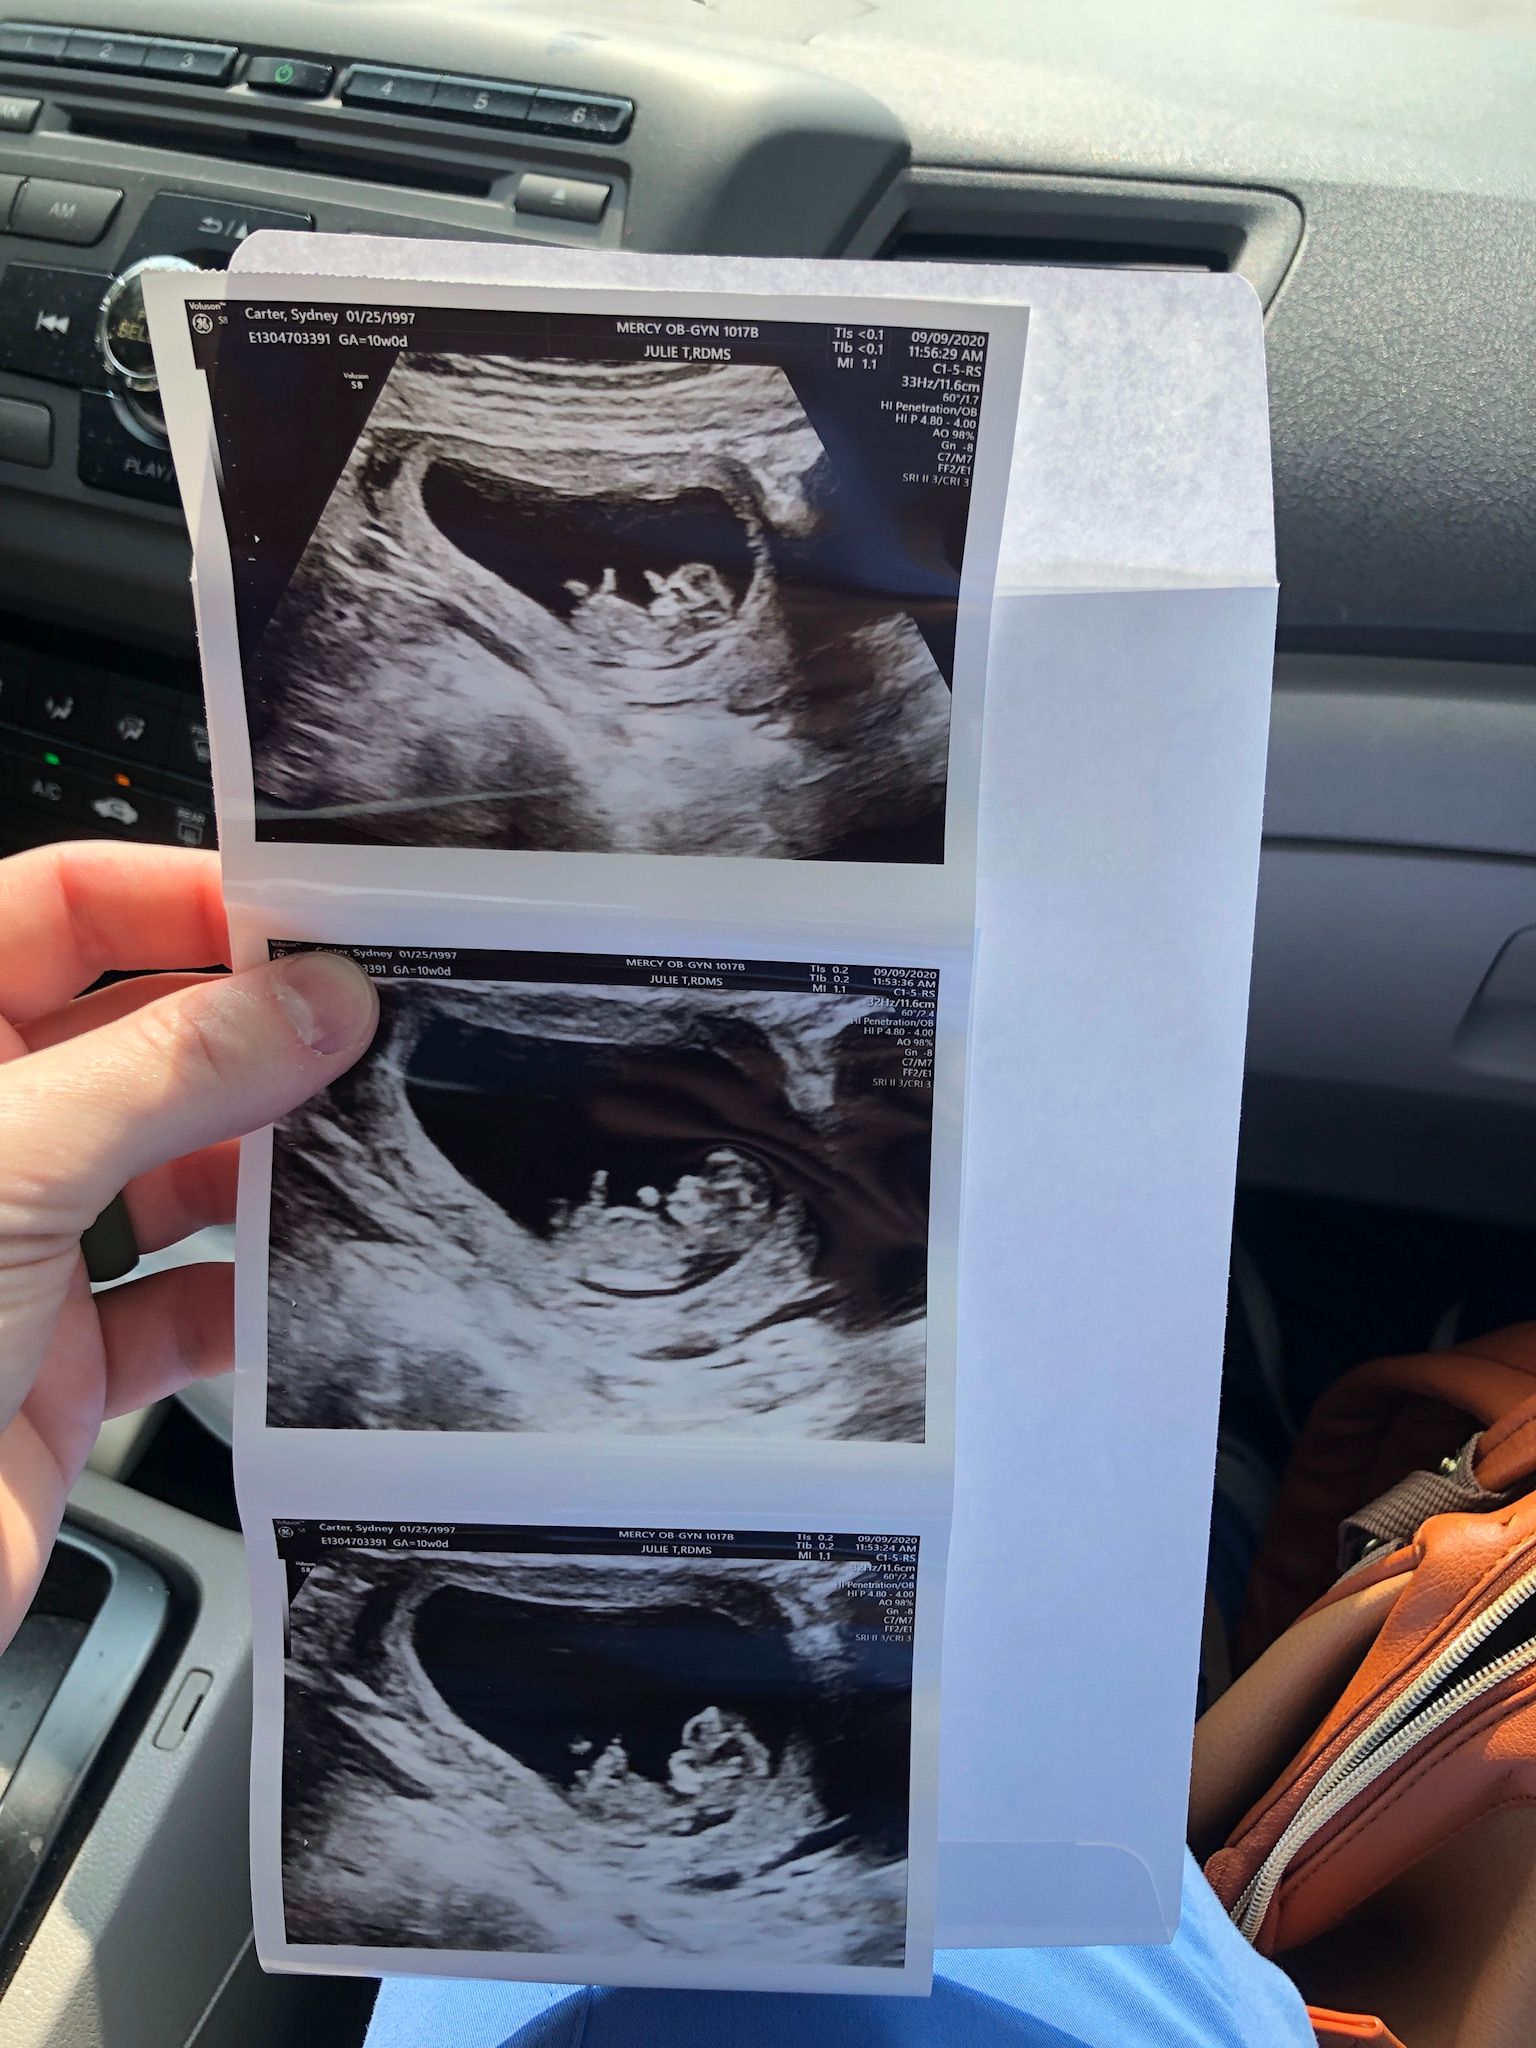

September 9: Back to Dr. Phillips!! 10 weeks

I was extremely nervous for this appointment.. Logan happened to get done with his patient early and was able to come! This was a huge relief for me. I swung down to the school and picked him up and we headed over to Mercy hospital. We went back and got our ultrasound first - and there was the cutest little bean dancing around! It was so crazy and funny to watch, it was fist bumping all around and kicking their legs. It was really great to have Log be there to actually see! We met with Dr. Phillips after, and man I love her! She has been a HUGE support to me, especially when things were really rough. She was thrilled with how things were looking and was very happy for us. We will be back in 3 weeks for another check. :)